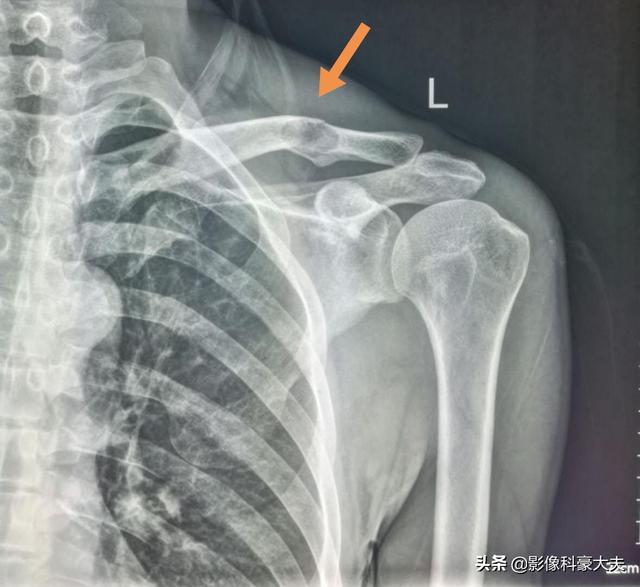

Métastase claviculaire d'un carcinome peu différencié ayant survécu à la tumeur pendant 5 ans.

Il s'agit d'un homosexuel de 58 ans qui a commencé à ressentir une douleur persistante lorsque son épaule a été légèrement étirée, et les radiographies ont révélé des foyers hypodenses :

Il s'agissait d'une fracture pathologique causée par des forces externes mineures sur la base d'une métastase osseuse. Une ponction a été effectuée et la pathologie était une métastase osseuse d'un adénocarcinome pulmonaire peu différencié.